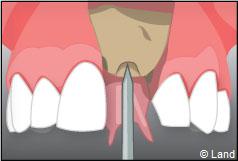

Le chirurgien-dentiste après une anesthésie locale pratique une incision, puis il décolle la gencive pour accéder à l’os alvéolaire.

Ensuite il prépare l’emplacement de l’implant dans l’os en passant plusieurs forets de diamètre croissant. Le forage de l’os se fait à vitesse maîtrisée et lente sous irrigation, pour respecter la structure osseuse et éviter tout échauffement de celle-ci. Le praticien arrête lorsqu’il a obtenu un puits d’un diamètre très légèrement inférieur à l’implant à poser.

L’implant est placé dans l’os le plus souvent par vissage et doit avoir une liaison forte avec l’os. Le praticien replace alors la gencive et pose des points de suture.